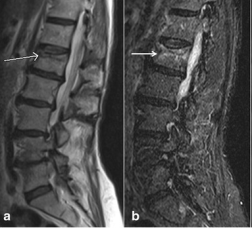

What's the Diagnosis?